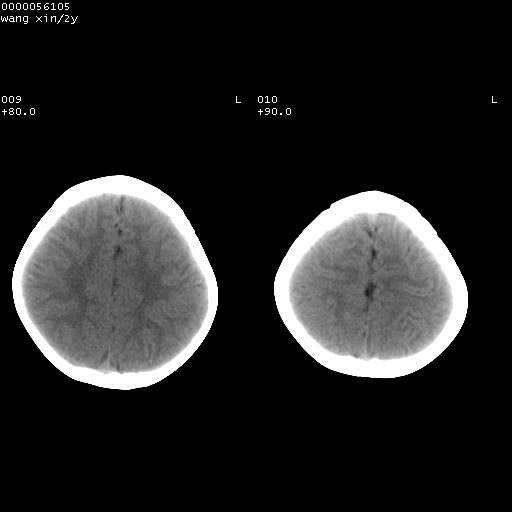

标题: PED1611:F,2Y。右侧额部小包块,光整,质硬,边界清楚,无 [打印本页]

标题: PED1611:F,2Y。右侧额部小包块,光整,质硬,边界清楚,无

右额骨内板压迫性变薄,呈椭圆形膨胀性骨吸收和低密度区,其间可见小斑片状致密影,-支持表皮样囊肿